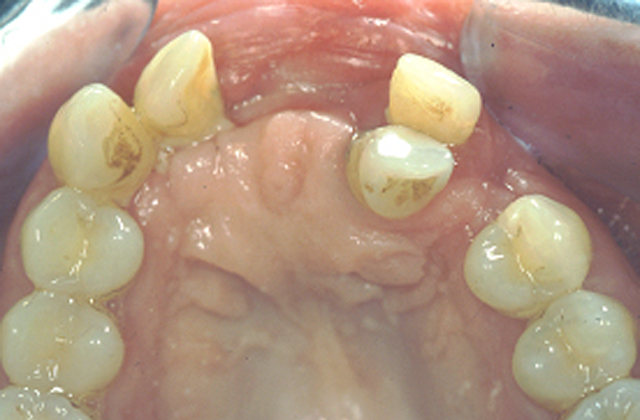

• Avant

Suite à la perte par traumatisme, de cinq dents antérieures, la mise en place de 3 implants va nous permettre de reconstruire le sourire de cette patiente